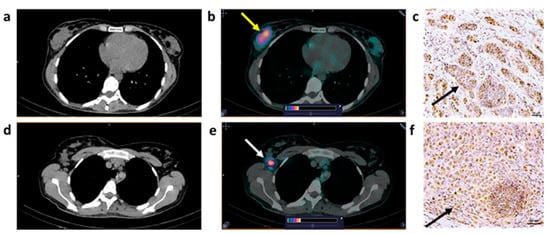

3.4. Imaging Data Analysis

3.5. Immunohistochemical Staining

| P1 | 68 | PAA G2 GS 7 (3+4) PSA = 11.4 | T2N0M0 | 1.67 (1.6 × 2.5) | 7.3 | 2+ |

| P2 | 56 | PAA G2 GS 7 (3+4) PSA = 9 | T2aN0M0 | 0.78 (1.7 × 2) | 6.5 | 0 |

| P3 | 68 | PAA G5 GS 9 (4+5) PSA = 207.6 | T3aN0M0 | 1.21 (4.1 × 2.8) | 10.9 | No material |

| P4 | 65 | PAA G1 GS 6 (3+3) PSA = 9.25 | T1bN0M0 | 1.14 (1.8 × 2.0) | 4.2 | 1+ |

| P5 | 66 | PAA G1 GS 6 (3+3) PSA = 11 | T2N0M0 | No accumulation | 3+ | |

| P6 | 70 | PAA G2 GS 7 (4+3) PSA = 7.93 | T2aN0M0 | No accumulation | 0 | |

| B1 | 34 | IC NST G2 | T2N0M0 | T: 1.41 (2.8 × 2.2) | 2.2 | T: 3+ | T2N0M0 |

| B2 | 41 | IC NST G2 | T2N2M0 | T: 1.75 (3.8 × 2.2) LNM: 1.8 (1.3) | T: 35 LNM: 16.3 | T: 1+ LNM: 2+ | T2N3M0 |

| B3 | 40 | IC NST G2 | T2N0M0 | T: 0.87 (5.1 × 2.2) LNM: 1.8 (1.4) | T: 10.8 LNM: 7.1 | T: 0 LNM:1+ | T3N3M0 |

| B4 | 69 | ILC G1 | T2N0M0 | T: 0.57 (6.8 × 3.2) LNM: 0.58 (2.5) | T: 7.8 LNM: 6 | T: 1+ LNM: 1+ | T2N1M0 |

| B5 | 56 | IC NST G2 | T2N1M0 | T: 0.87 (4.0 × 1.7) LNM: 1.8 (2.3) | T: 14.5 LNM: 11.3 | T: 0 LNM: 0 | T2N1M0 |

| B6 | 50 | IC NST G1 | T1N0M0 | T: 0.43 (1.5 × 1.5) | T: 4.3 | T: 3+ | T1N0M0 |

| B7 | 62 | IC NST G2 | T1N0M0 | T: 0.50 (1.5 × 1.4) | T: 2.7 | T: 1+ | T1N0M0 |